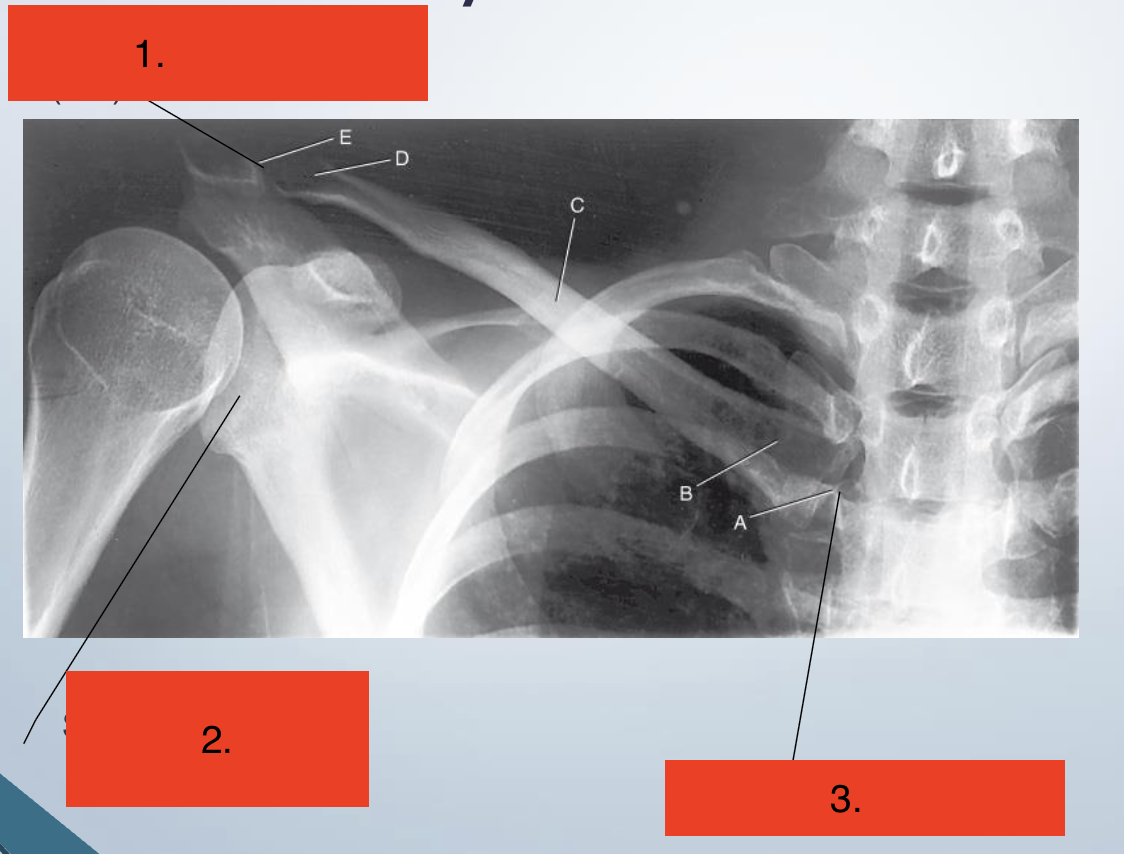

Label the joints

Acromioclavicular (AC)

Scapulohumeral

Sternoclavicular (SC)